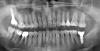

roman01972 Опубликовано 9 февраля, 2013 Поделиться Опубликовано 9 февраля, 2013 (изменено) Уважаемые доктора, помогите, надоел карман рядом с 46 зубом (по утрам промываю его ирригатором), решил что что-то надо с ним делать, доктор, у которого раньше делал имплантацию двух зубов, предлогает исправить пломбу на соседнем зубе. есть ли какие нибудь еще варианты в моем случае? пусть даже более сложные, я имею в виду лоскутная операция или еще что-то подобное с восстановлением кости между зубами. вот ссылка на снимок объем 1,7 мбhttp://files.mail.ru...B23F09CEF963D74 Изменено 9 февраля, 2013 пользователем roman01972 Ссылка на комментарий

IvanK Опубликовано 9 февраля, 2013 Поделиться Опубликовано 9 февраля, 2013 Контактный пункт необходимо переделать + консультация ортопеда, пародонтолога Ссылка на комментарий

Bier Опубликовано 9 февраля, 2013 Поделиться Опубликовано 9 февраля, 2013 Восстановить кость - сомнительно. Переделать контактный пункт надо, можно попробовать заместить дефект кости синтетической костью, но шансов мало. Ссылка на комментарий